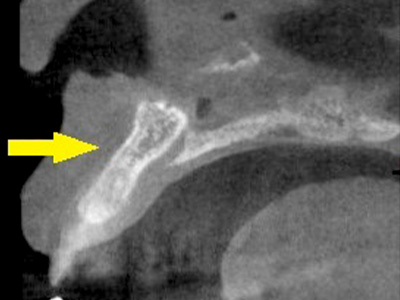

CTで見ると、骨吸収の様子が良く分かり、下顎骨の中を通る神経近くまで骨がありませんでした(黄色矢印)。

さらに、CTで別な方向から見ると、黄色矢印のように骨が吸収されていて、緑色矢印で示される神経の通る管に迫り、インプラントが埋入できるような骨量はありませんでした。